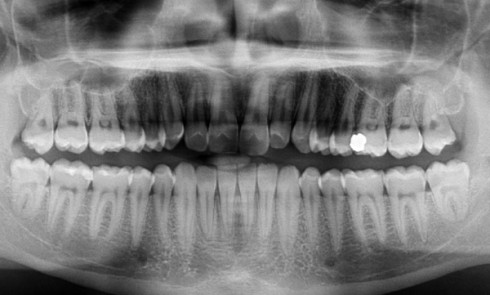

Article réservé à nos abonnés Discussion autour d’un cas complexe d’inclusions multiples atypiques

En l’absence d’obstacle mécanique et d’antécédents médico-chirurgicaux particuliers, le cas décrit précédemment évoque un tableau clinico-radiologique de défaut primaire d’éruption...